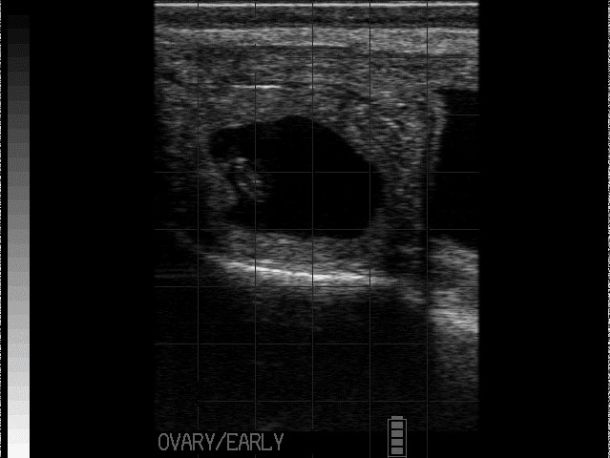

The most common ovarian abnormality seen in cows are ovarian cysts that have resulted from anovulation. Traditionally, authors subdivided ovarian cysts into follicular and luteal depending on their ultrasonographic appearance4.

Follicular cysts are typically large, thin-walled (<2-3mm), round, black structures that are often single but can be multiple (see Photo 1)2,4. Traditionally, follicular cysts were defined by being greater than 25mm in diameter and persisting for longer than 10 days but recent work would indicate that follicular cysts can be present and only measure 16-17mm in diameter2. Cows with follicular cysts will have low peripheral progesterone concentrations and typically present anoestrous but can be nymphomaniacal if the cyst is actively secreting oestradiol4. However, that stated, follicular cysts are still dynamic structures which can luteinise (forming a luteal cyst), or become inactive and regress. In situations where they have begun to regress, the cystic structures can be noted in cows who have started to cycle again (i.e., some of these cows will have CLs) or even those cows who have become pregnant.

Luteal cysts are typically grey, thick-walled (>3mm walls), large fluid-filled structures (≥ 25mm) that are often single2. As noted, luteal cysts result from luteinisation of follicular cysts that fail to ovulate. Cows with luteal cysts will have high peripheral progesterone concentrations and typically present as anoestrous4.